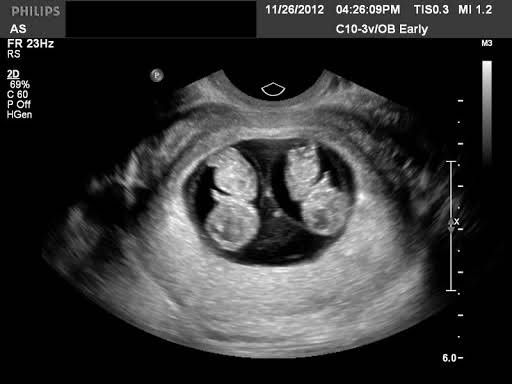

"Đi gặp 2 bé con nhỏ trong bụng em bé này" vừa nói hắn vừa xoa xoa cái bụng của anh vì anh mang thai đôi nên bụng anh đã to hơn người mang thai đơn bình thường.Anh nghe hắn nói vậy thì hạnh phúc lắm chủ động thơm lên má hắn 1 cái rồi cùng hắn đi ăn tối uống sữa để ngày mai còn đi gặp 2 bé con của mình nữa

"Vậy đi vào đây ta khám cho nhé" bác Phúc kéo tai anh đi vào phòng siêu âm.

Trong phòng siêu âm là âm thanh nhịp tim của 2 bé con đang đập rất mãnh liệt có lẽ 2 bé con biết rằng anh đang buồn nên 2 bé đang cố làm cho anh vui. Đột nhiên bác Phúc cười lớn rồi nói "là 2 cậu hoàng tử đấy nhé". Anh nghe thấy giới tính của con thì hạnh phúc lắm nhưng sẽ hạnh phúc hơn khi hắn cũng ở đây nghe giới tính của con và cả nhịp tim nữa nhưng có lẽ điều đó là quá xa vời với anh hiện tại rồi. Ở thời điểm này anh biết cuộc sống của anh sẽ trở về quỹ đạo cũ và rất có thể nó sẽ rất tệ.